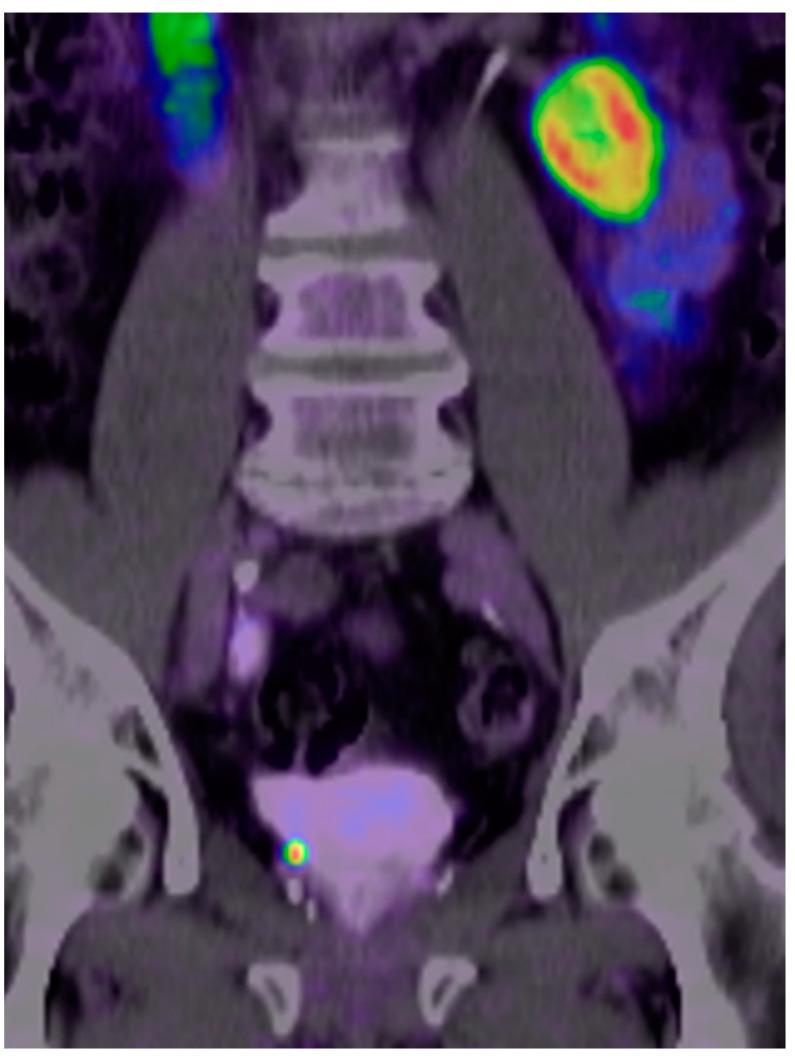

This study aimed to compare the diagnostic performance of [18F]PSMA-1007 positron emission tomography/computed tomography (PET/CT) (18F-PSMA) and [68Ga]Ga-PSMA-11 PET/CT (68Ga-PSMA) by identifying prostate-specific antigen (PSA) threshold levels for optimal detecting recurrent prostate cancer (PC) and to compare both methods. Retrospectively, the study included 264 patients. The performances of 18F-PSMA and 68Ga-PSMA in relation to the pre-scan PSA were assessed by receiver operating characteristic (ROC) curve. 18F-PSMA showed PC-lesions in 87.5% (112/128 patients), while 68Ga-PSMA identified them in 88.9% (121/136). For 18F-PSMA biochemical recurrent (BCR) patients treated with radical prostatectomy (78/128, patient group: F-RP), a PSA of 1.08 ng/mL was found to be the optimal cut-off level for predicting positive and negative scans (AUC = 0.821; 95%, CI: 0.710−0.932), while for prostatectomized 68Ga-PSMA BCR-patients (89/136, patient group: Ga-RP), the cut-off was 1.84 ng/mL (AUC = 0.588; 95%, CI: 0.410−0.766). In patients with PSA < 1.08 ng/mL (F-RP) 76.3% and <1.84 ng/mL (Ga-RP) 78.6% scans were positive, whereas patients with PSA ≥ 1.08 ng/mL (F-RP) or 1.84 ng/mL (Ga-RP) had positive scan results in 100% and 91.5% (p < 0.001/p = 0.085). The identified PSA thresholds for PSMA-mappable PC lesions in BCR-patients (RP) showed a better separation for 18F-PSMA with regard to the distinguishing of positive and negative PC-lesions compared to 68Ga-PSMA. However, the two PSMA PET/CT tracers gave similar overall findings.

本研究旨在通过确定前列腺特异性抗原(PSA)阈值水平以优化检测复发性前列腺癌(PC),比较[18F]PSMA - 1007正电子发射断层扫描/计算机断层扫描(PET/CT)(18F - PSMA)和[68Ga]Ga - PSMA - 11 PET/CT(68Ga - PSMA)的诊断性能,并比较这两种方法。该研究回顾性纳入了264例患者。通过受试者操作特征(ROC)曲线评估18F - PSMA和68Ga - PSMA相对于扫描前PSA的性能。18F - PSMA在87.5%(112/128例患者)中显示出PC病变,而68Ga - PSMA在88.9%(121/136)中识别出这些病变。对于接受根治性前列腺切除术的18F - PSMA生化复发(BCR)患者(78/128,患者组:F - RP),发现PSA为1.08 ng/mL是预测扫描阳性和阴性的最佳临界值(AUC = 0.821;95%,CI:0.710 - 0.932),而对于接受前列腺切除的68Ga - PSMA BCR患者(89/136,患者组:Ga - RP),临界值为1.84 ng/mL(AUC = 0.588;95%,CI:0.410 - 0.766)。在PSA < 1.08 ng/mL(F - RP)的患者中,76.3%的扫描为阳性,在PSA < 1.84 ng/mL(Ga - RP)的患者中,78.6%的扫描为阳性,而PSA≥1.08 ng/mL(F - RP)或1.84 ng/mL(Ga - RP)的患者中,扫描阳性结果分别为100%和91.5%(p < 0.001/p = 0.085)。在BCR患者(RP)中,确定的可通过PSMA映射的PC病变的PSA阈值显示,与68Ga - PSMA相比,18F - PSMA在区分PC病变阳性和阴性方面具有更好的区分度。然而,两种PSMA PET/CT示踪剂的总体结果相似。